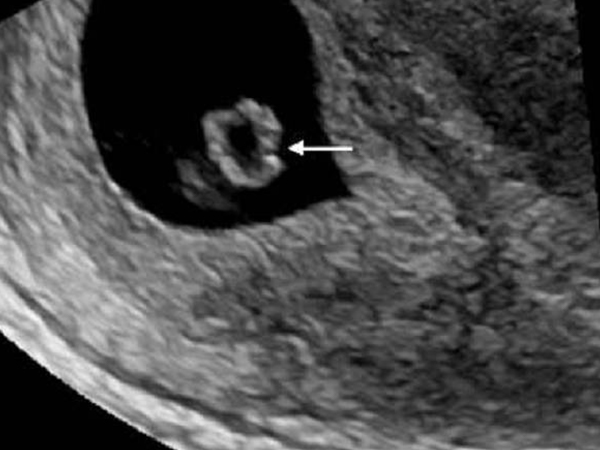

女性在怀孕后,受精卵发育成胚胎着床,会先形成孕囊,这时的孕囊是一个空壳,然后在这个空壳的内部会相继出现卵黄囊、胎心胎芽,但是如果在做B超时发现出现了卵黄囊,却没有出现胎芽的话,就意味着胚胎发育可能出现了问题,很有可能会停育。

卵黄囊一般出现在孕4~5周的时候,是胚胎早期形成血管和组织的部位,同时有着供血、新陈代谢、免疫和营养的作用,而胎芽一般出现的时间是孕6~7周的时候,胎芽慢慢的会发育成胎心,这是胎儿形成的过程,因此卵黄囊和胎芽的发育对胎儿发育来说都是十分重要的。

以上三点就是孕囊内有了卵黄囊却迟迟没有胎芽的主要原因,因此一般建议在孕6~7周b超没有看到胎芽的话,可以再等一周进行复查,在孕8周时检查如果有胎芽则发育为正常,如果这时候还没有胎芽,则考虑发育异常,需终止妊娠。